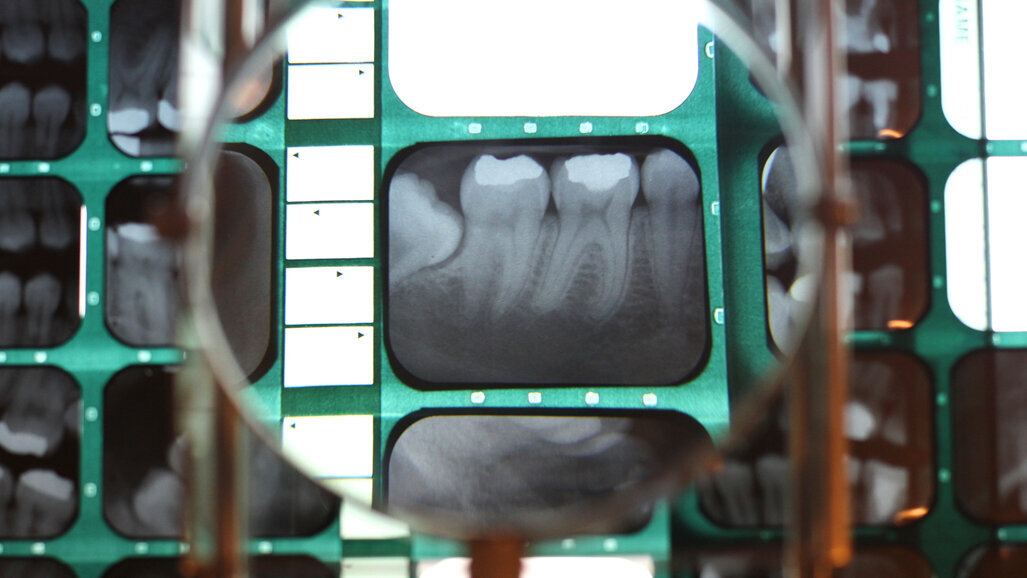

KOPENHAGEN, Danska: Istraživači u Turskoj analizirali su u kojoj mjeri algoritmi umjetne inteligencije (AI) mogu identificirati parodontopatije iz dvodimenzionalne rendgenske snimke s ugrizom u traku (bite wing). Prema istraživanju čiji su rezultati predstavljeni na skupu EuroPerio10 u Kopenhagenu 16. lipnja, AI sustav može identificirati parodontopatije koje mogu promaknuti stomatolozima.

Istraživanje su proveli istraživači sa Sveučilišta Eskisehir Osmangazi u Eskisehiru u Turskoj, a cilj je bio procijeniti sposobnost umjetne inteligencije da odredi parodontni status s pomoću rendgenskih snimki s ugrizom u traku. Upotrijebilo se ukupno 434 rendgenskih snimki s ugrizom u traku pacijenata s parodontitisom, a snimke je s pomoću konvolucijske neuronske mreže analizirao iskusni kliničar u pogledu totalnog gubitka alveolarne kosti, horizontalnog i vertikalnog gubitka kosti, furkacijskih defekata i kamenca oko gornjih i donjih zubi.

U usporedbi s procjenom kliničara, AI je dobio visoku ocjenu i u osjetljivosti i u preciznosti u identificiranju ukupnog gubitka alveolarne kosti i horizontalnog gubitka kosti, ali nije mogao identificirati vertikalni gubitak kosti. Ponderirani prosjeci osjetljivosti i preciznosti u prepoznavanju zubnog kamenca i furkacijskih defekata u usporedbi s procjenom kliničara, bili su 0,82 i 0,66.

Dr. Yavuz komentirao je u priopćenje za javnost: “Naše istraživanje pokazuje potencijal umjetne inteligencije za automatsku identifikaciju bolesti parodonta koje bi se inače mogle previdjeti. Time bi se mogla smanjiti izloženost zračenju izbjegavanjem ponavljanja pregleda, spriječiti tiho napredovanje parodontopatija te omogućiti ranije liječenje.” Dodao je da rezultati ilustriraju “da je umjetna inteligencija u stanju konpenzirati mnoge vrste nedostataka 2D snimki, što bi moglo pomoći u dijagnostici parodontitisa”.